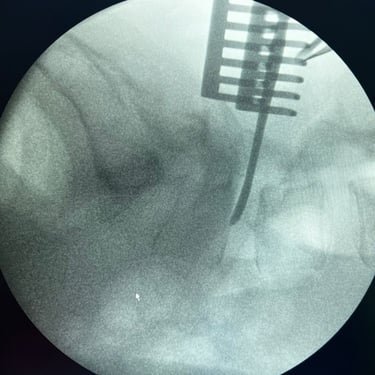

Cirugía de Hernia Lumbar | Discectomía Lumbar

La hernia lumbar ocurre cuando parte del disco intervertebral se desplaza y comprime las raíces nerviosas, generando dolor lumbar, ciática y debilidad en las piernas. Cuando el tratamiento médico no alivia los síntomas, la opción más efectiva es la discectomía lumbar, una cirugía destinada a retirar el fragmento herniado del disco que presiona el nervio. Este procedimiento, realizado mediante técnicas microquirúrgicas, busca aliviar el dolor y recuperar la función neurológica. La recuperación suele ser rápida, permitiendo al paciente reincorporarse gradualmente a sus actividades. La cirugía ofrece altas tasas de éxito y mejora significativa de la calidad de vida.